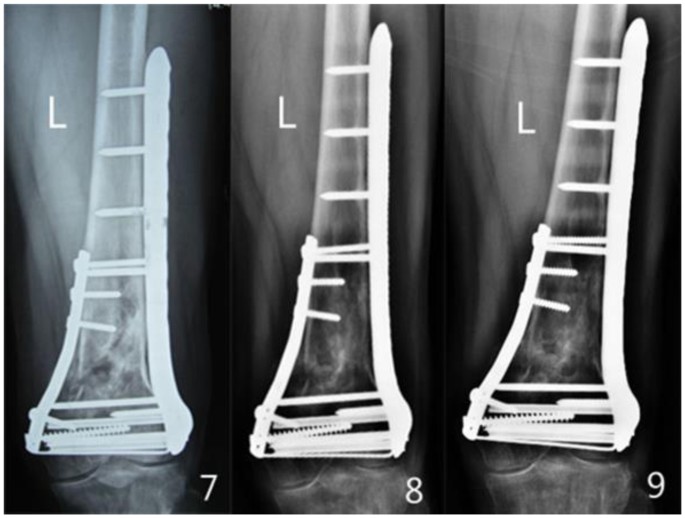

All patients were followed up for 12 to 48 months. The follow-up records of one patient of the double-plate group are shown in Figs 1–5 and those of one patient of the single plate group are shown in Figs 6 and 7. One patient in each group died one year and a half after the operation due to other causes. There were 58 patients and 60 cases of distal femoral fractures in total, of which one patient had bilateral distal femoral fractures both fixed by lateral plate and the other one with bilateral distal femoral fractures had a single plate on the right distal femur and double plates on the left. The age distribution of patients in the single-plate group and the double-plate group is shown in Table 1. There was no significant difference between the two groups (p = 0.330).

Plain film was performed every 3 months after operation for monitoring the fracture healing and whether there was loss of reduction and rupture of plate(s) and screws. Each patient was followed up until the fracture union and no less than one year. According to the plain film and condition of the patient, it was determined when partially loaded walking should be started and how to exercise step by step. Knee function was evaluated by Kolmert’ standard, one year after surgery.